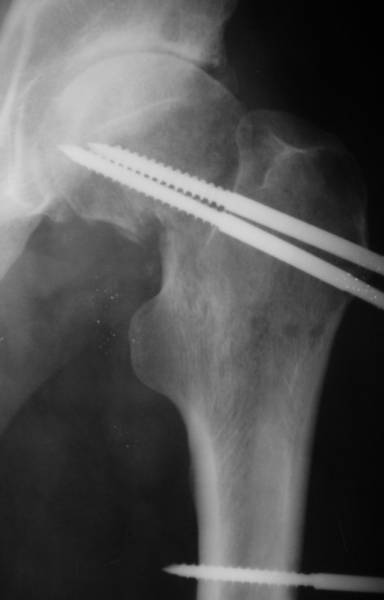

Насчет 8 см согласен с А.Н. Челноковым, это наверное ортопедическое за счет приводящей, сгибательной контрактуры и, возможно, колена. на ликвидацию укорочения у нас обычно уходит около 2-х нед. снимки в приложении, возможно не очень показательные, но других с ходу не нашел, завтра еще поищу.

Еще пара фото, ситуация несколько иная, задачи те же, открытое вправление застарелого вывиха в 2002, молодой возраст. Сейчас госпитализирована для эндопротезирования.